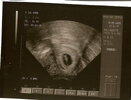

Trochę sie wstrzymywałam gdyż pierwsza ciaza po prostu nie wyszla,teraz biore duphaston 2 razy dziennie, i mam nadzieje ze już będzie dobrze, w pn widzialam małego człowieczka i slyszalam bijace serduszko

juz ustawiony do góry nogami

widac raczki i 2 zlaczone nóżki

termin 1 stycznia według OM